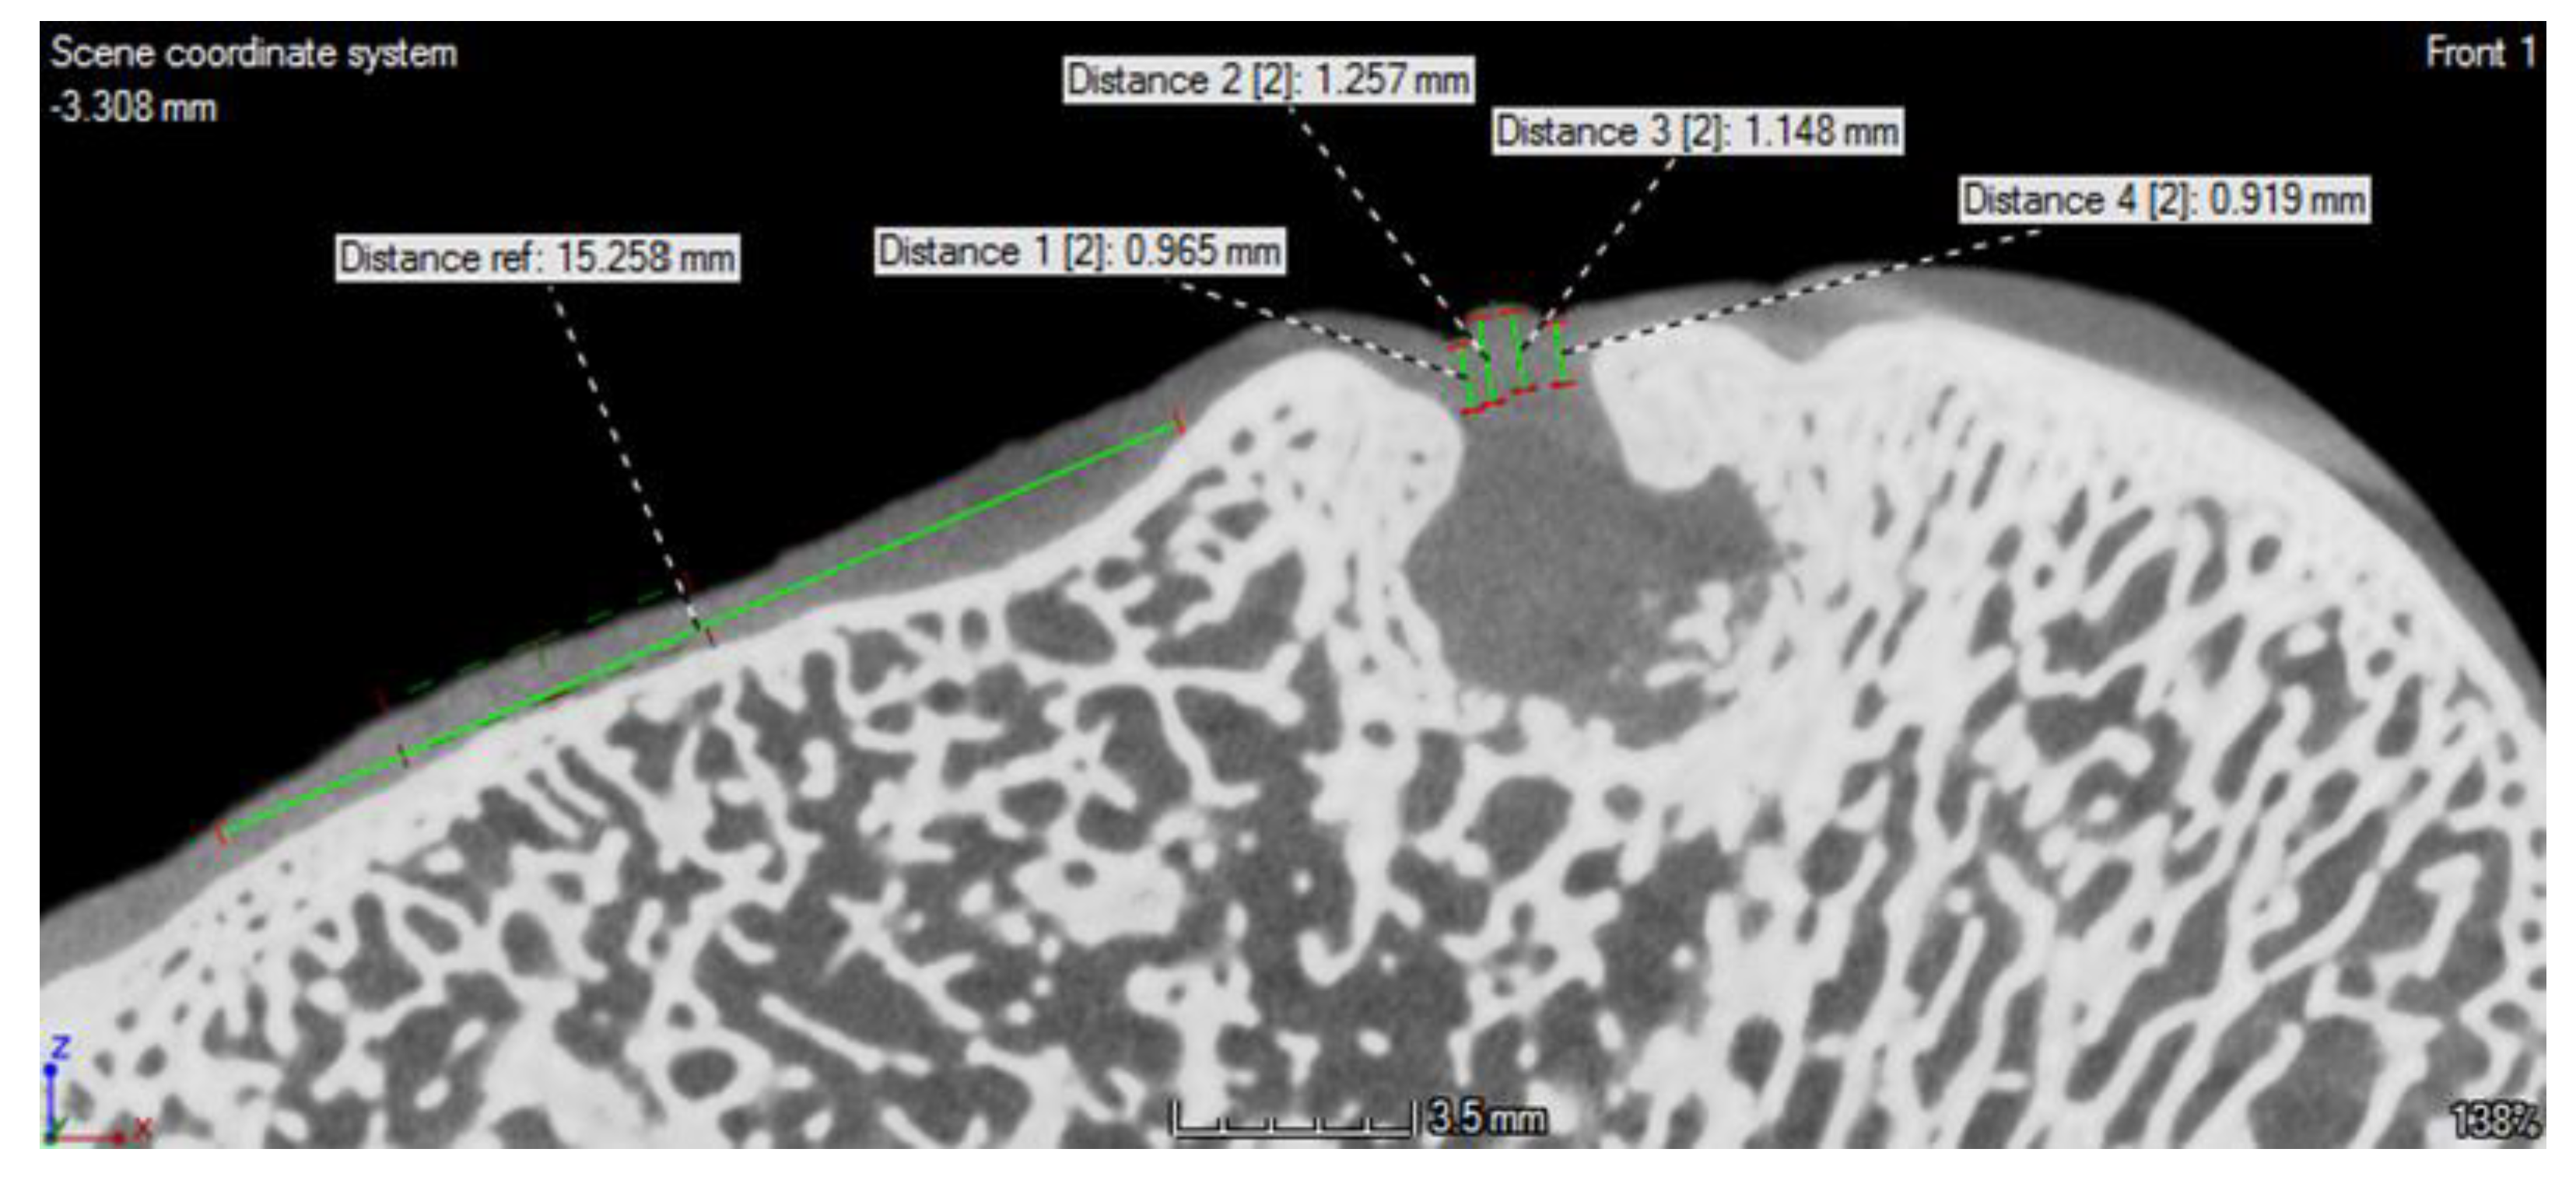

3.3. CT Evaluation

3.4. MRI Evaluation